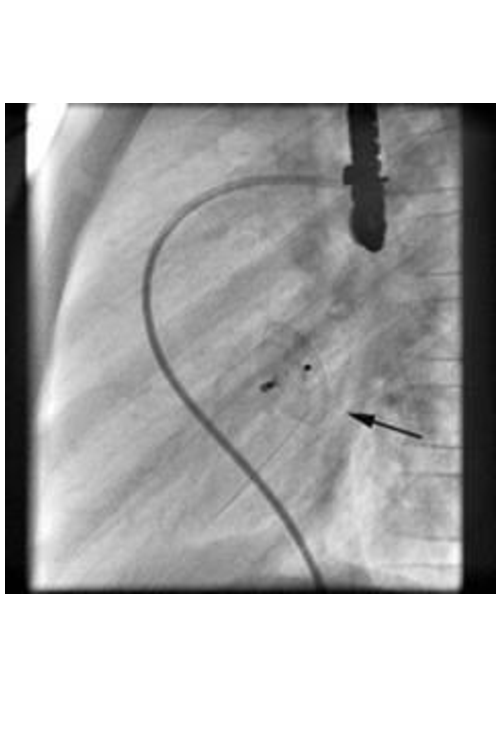

The catheter is first inserted into the right ventricle via the inguinal vein and into the left ventricle via the ASD. The ASD is then precisely measured using a filled balloon catheter (balloon sizing). The appropriate occluder is selected according to the size determined. During implantation, the umbrella is folded in such a way that it can be pushed through a thin tube (sheath) via the inguinal vein into the heart. The umbrella only takes on its actual shape once it has been pushed out of the sheath. The final position is then checked by a cardiac ultrasound and the occluder can then be unscrewed from the retaining cable. The occluder remains in the heart for life and is overgrown with the patient's own heart tissue.